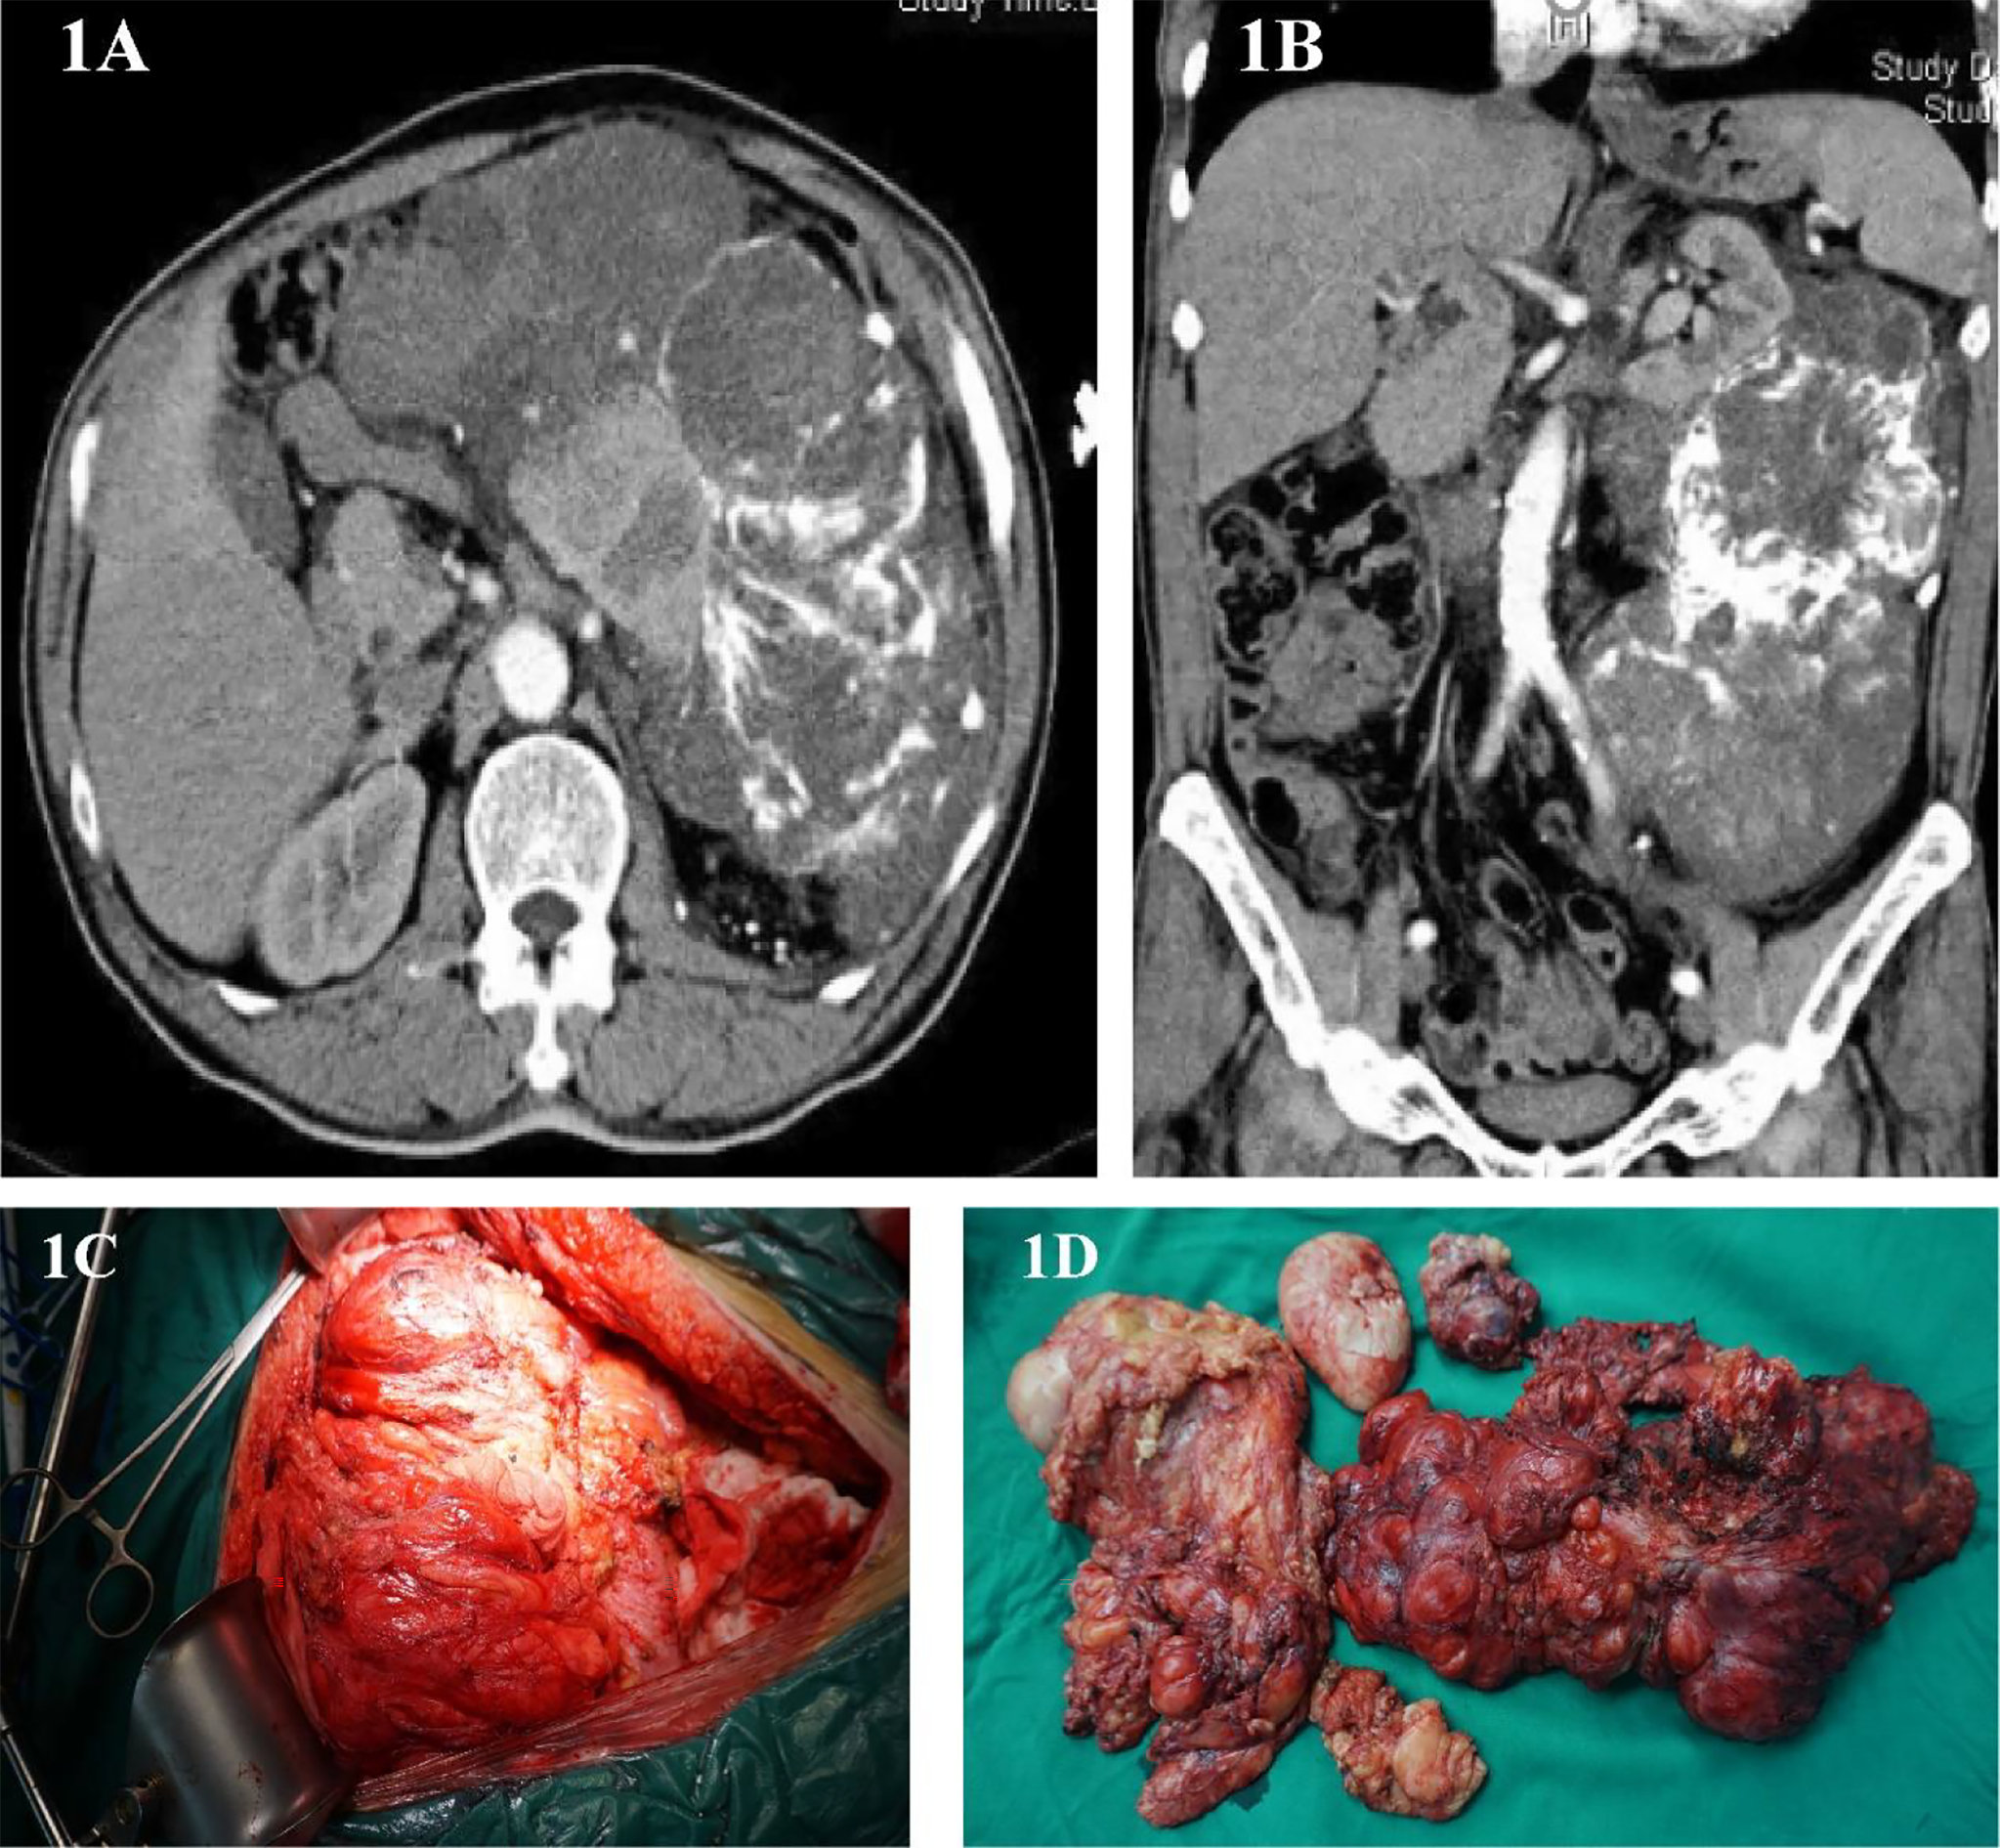

This is a 60-year-old male who found an abdominal mass for 8 months. His waist circumference gradually increased, during which no treatment was taken. The patient was in good health and had no history of cancer. In March 2012, he was hospitalized due to upper abdomen discomfort. Physical examination of his upper abdomen revealed a huge mass. Tumor markers such as carcinoembryonic antigen (CEA), carbohydrate antigen199 (CA-199), carbohydrate antigen 125 (CA125), carbohydrate antigen 50(CA50), alpha-fetoprotein (AFP) are all within the normal range. Abdominal CT scans showed a huge lump around the left kidney, considering malignant tumors (Figures 1A, B). On March 14, 2012, we performed a radical surgical resection on the patient. Operation name: retroperitoneal tumor resection+ left nephrectomy+ left adrenalectomy. Part of the tumor is tough, most of it is hard and bony, which surrounds the kidney and adheres to the surface of the kidney. During the operation, the kidney could not be stripped, and it is suspected that the sarcoma has invaded the kidney (Figure 1C). In order to maximize the marginal negative resection, so as to reduce the recurrence rate of tumor after surgery. The surgeon decided to perform combined organ resection and removed the left kidney and left adrenal gland (Figure 1D). The postoperative pathology was dedifferentiated liposarcoma, and the dedifferentiated component was like myxofibrosarcoma, which invaded the kidney tissue, and did not involve the ureteral stump and adrenal gland. Tumor components were seen around the renal hilar vessels. The patient’s vital signs were stable after surgery and was discharged from hospital on March 22, 2012.

Figure 1

(A, B) Abdominal image before the first operation. (C) Intraoperative photos. (D) Surgical piece of the dedifferentiated liposarcoma.